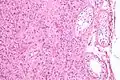

![]() Micrograph showing a cluster of Leydig cells (center of image). H&E stain. | |

The mammalian Leydig cell is a polyhedral epithelioid cell with a single eccentrically located ovoid nucleus. The nucleus contains one to three prominent nucleoli and large amounts of dark-staining peripheral heterochromatin. The acidophilic cytoplasm usually contains numerous membrane-bound lipid droplets and large amounts of smooth endoplasmic reticulum (SER). Besides the obvious abundance of SER with scattered patches of rough endoplasmic reticulum, several mitochondria are also prominent within the cytoplasm. Frequently, lipofuscin pigment and rod-shaped crystal-like structures 3 to 20 micrometres in diameter (Reinke crystals) are found. These inclusions have no known function, are found in less than half of all Leydig cell tumors, but serve to clinch the diagnosis of a Leydig cell tumor.[1][2] No other interstitial cell within the testes has a nucleus or cytoplasm with these characteristics, making identification relatively easy.